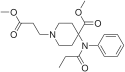

Anilidopiperidines

Phenylpiperidines